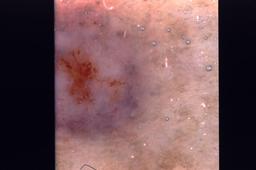

{

"age_approx": 85,

"anatom_site_general": "head/neck",

"concomitant_biopsy": true,

"dermoscopic_type": "contact non-polarized",

"diagnosis_1": "Indeterminate",

"diagnosis_2": "Indeterminate epidermal proliferations",

"diagnosis_3": "Solar or actinic keratosis",

"diagnosis_confirm_type": "histopathology",

"image_type": "dermoscopic",

"lesion_id": "IL_1144389",

"patient_id": "IP_2593801"